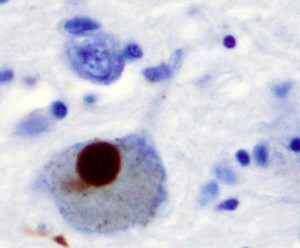

We know that in Parkinson’s Disease, cells that secrete the neurotransmitter dopamine in the depths of the brain die, affecting systems that control body movement, eye movements, emotional and cognitive functions. By the time someone starts to show motor symptoms, it is estimated that as many as 40-60% of these cells are already gone, and it is thought that the brain is able to compensate for their loss up until this point. Although scientists are still exploring the cause of this cell degeneration, one thing we do know is that when we look at these dopamine secreting cells from someone with Parkinson’s disease under a microscope, we can see what we call Lewy bodies. This is the brown blob seen inside the brain cell below. Lewy bodies can be thought of as junk and signal bad cell health.